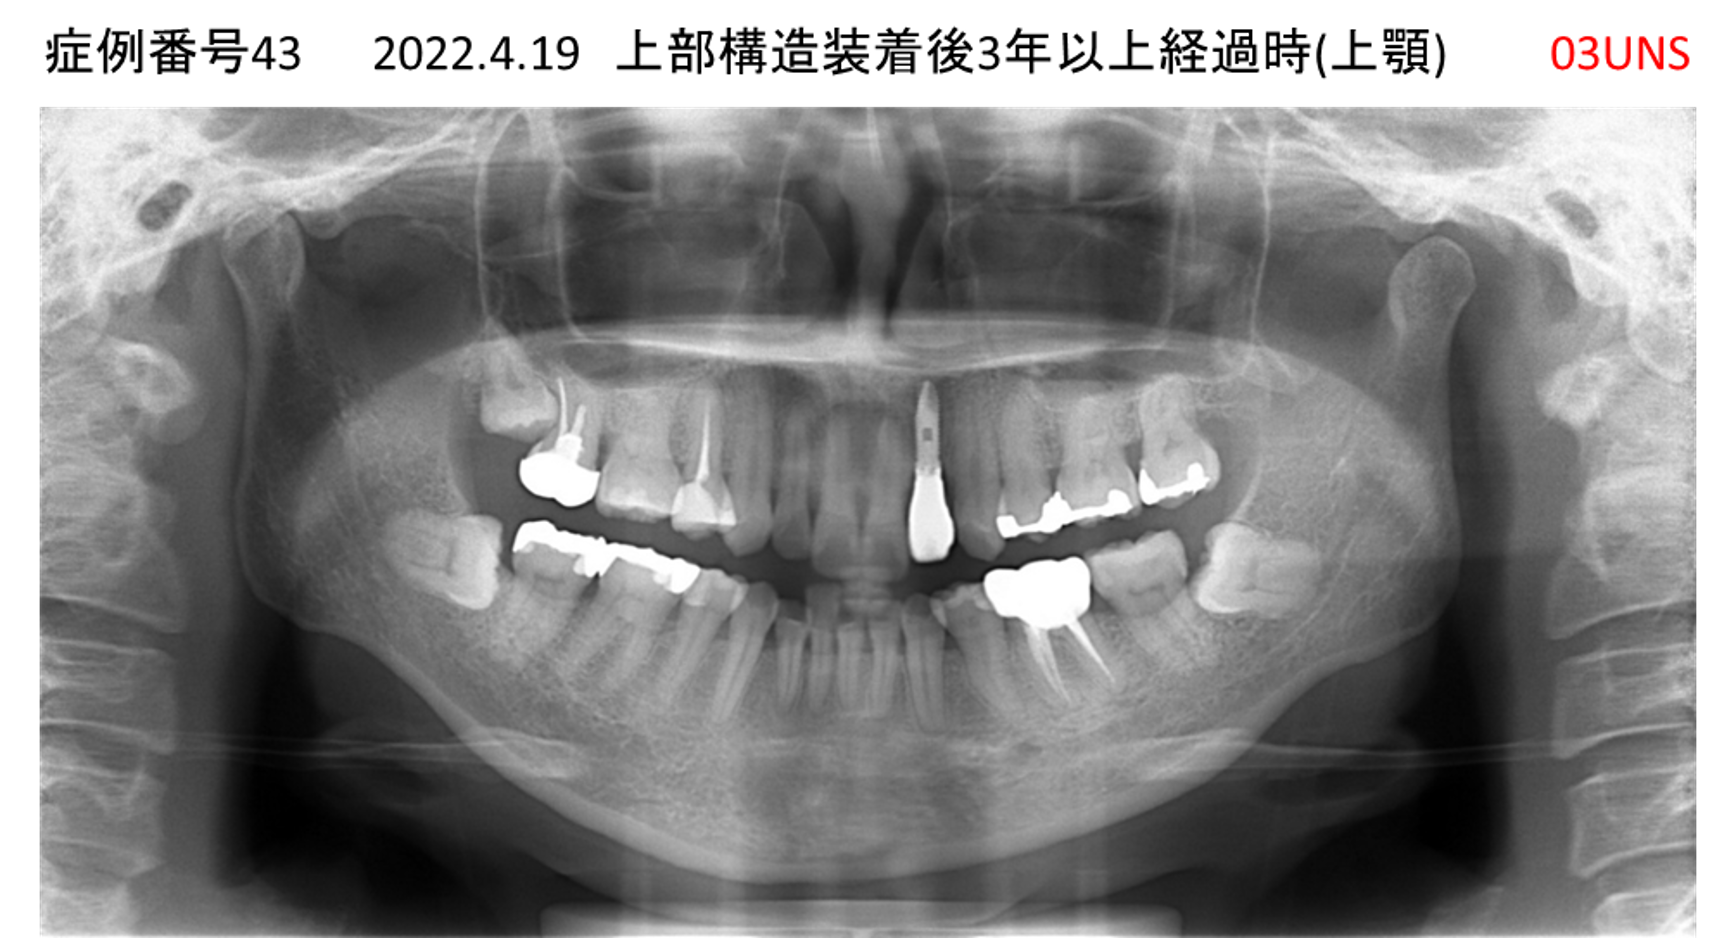

かめない/上の歯が揺れてきた患者様のインプラント症例

| 治療名称 |

インプラント |

| 治療費用 |

390万円+税 |

| 治療期間 |

6か月 |

| 患者さんの症状(主訴) |

かめない。上の歯が揺れてきた。 |

| 治療内容 |

サイナスリフト、抜歯即時インプラント |

| 治療結果 |

上の歯の揺れが収まった。噛めるようになった。食事がおいしい。 |

| 治療の注意点(リスク/副作用) |

インプラントが壊れたら再治療が必要 |